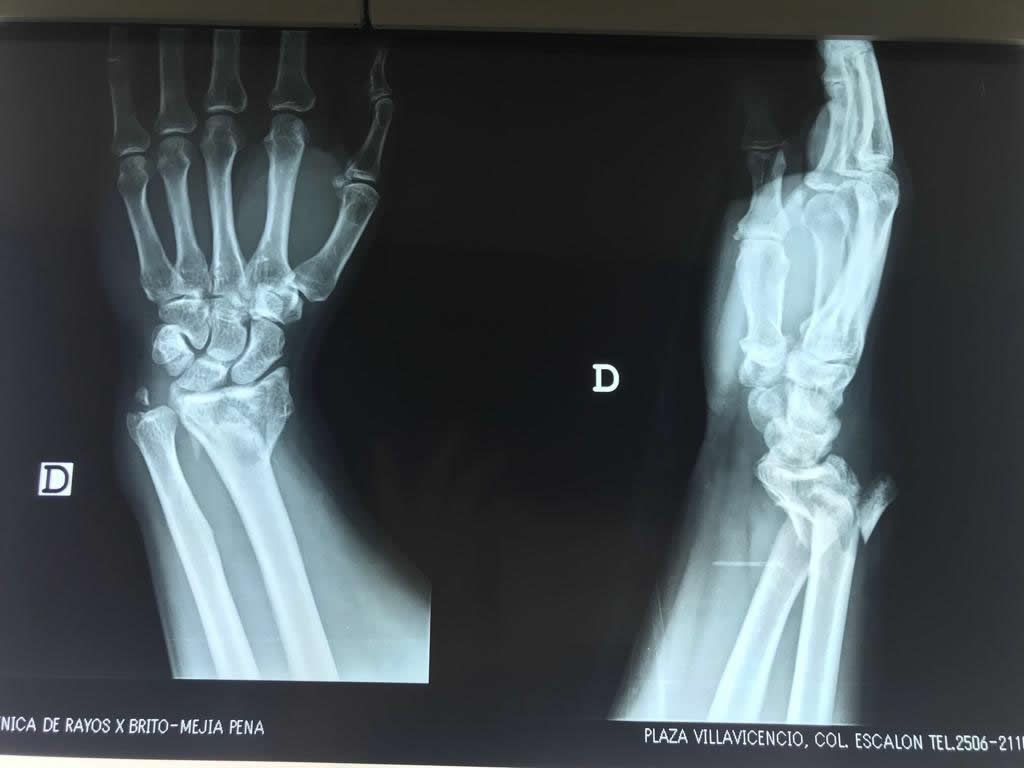

Cirugías de Calcaneo - Cirugías de Muñecas y Manos

Los procedimientos más comunes en cirugía de la mano son aquellos destinados a reparar traumatismos, incluyendo lesiones de tendones, nervios, vasos sanguíneos, y articulaciones; huesos fracturados; y quemaduras, cortes, y otros daños de la piel.